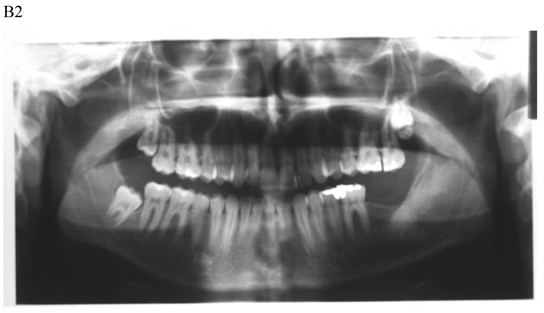

The treatment objective is restoring the morphology and function of the affected area. There are two basic surgical procedures, namely marsupialization (decompression) (Fig.1) and enucleation. Marsupialization, a relatively simple procedure, consists of surgically producing a “window” in the cystic wall to relieve intra-cystic tension. After this, the cystic cavity slowly decreases in size. The cavity is lightly packed with paraffin gauze until the line of junction between the cystic lining and the oral mucosa has healed. Three to six months later, enucleation is performed [16].

Figure 1

Dentigerous cyst affecting the left mandible of a 15-year-old boy treated by marsupiallization. At presentation, there was an acute infection in the area. A) Pre-operative radiographs: 1) Panoramic radiograph demonstrating a tooth within a large radiolucent area in the left mandible; 2) Axial CT scan demonstrating expansion of the body of the left mandible with very thin buccal and lingual cortices. A tooth is within the lumen; 3) Coronal CT of the mandible demonstrates an expansion of the ascending ramus of the left mandible with very thin cortical borders. A tooth is within the lumen. B. Postoperative radiographs: 1) Panoramic radiograph shortly post-marsupialization, extraction of tooth 37 that was adjacent the cyst as well as tooth 38 that was within the cyst; 2) Panoramic radiograph one year post-treatment. The radiodensity of the cystic area is similar to normal bone, indicating complete bone regeneration.

The notable disadvantages of the technique are: (a) it is a two-stage surgical procedure, (b) pathological tissue is left behind and a more sinister pathological process (i.e., squamous cell carcinoma) may be overlooked [21], and (c) in a large cystic cavity it takes a long period of time for the bone to regenerate.

Enucleation with primary closure is the treatment of choice [22]. It is a one-stage surgical treatment followed by periodic radiographic examinations at regular intervals to observe the progress of bone regeneration of the defect. It also allows pathologic examination of the entire specimen for histopathologic diagnosis. Enucleation can be done only when the jaw bone adjacent to the cyst is intact. If CT demonstrates erosions in the buccal or lingual cortices, marsupialization should be the treatment of choice (Fig. 1) [4].